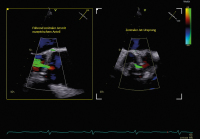

Aortenklappeninsuffizienz: Was gibt es Neues? // Aortic valve regurgitation – What do the 2021 guidelines say? What has changed from 2017?

Journal für Kardiologie - Austrian Journal of Cardiology 2024; 31 (5-6): 120-128 Volltext (PDF) Summary Abbildungen